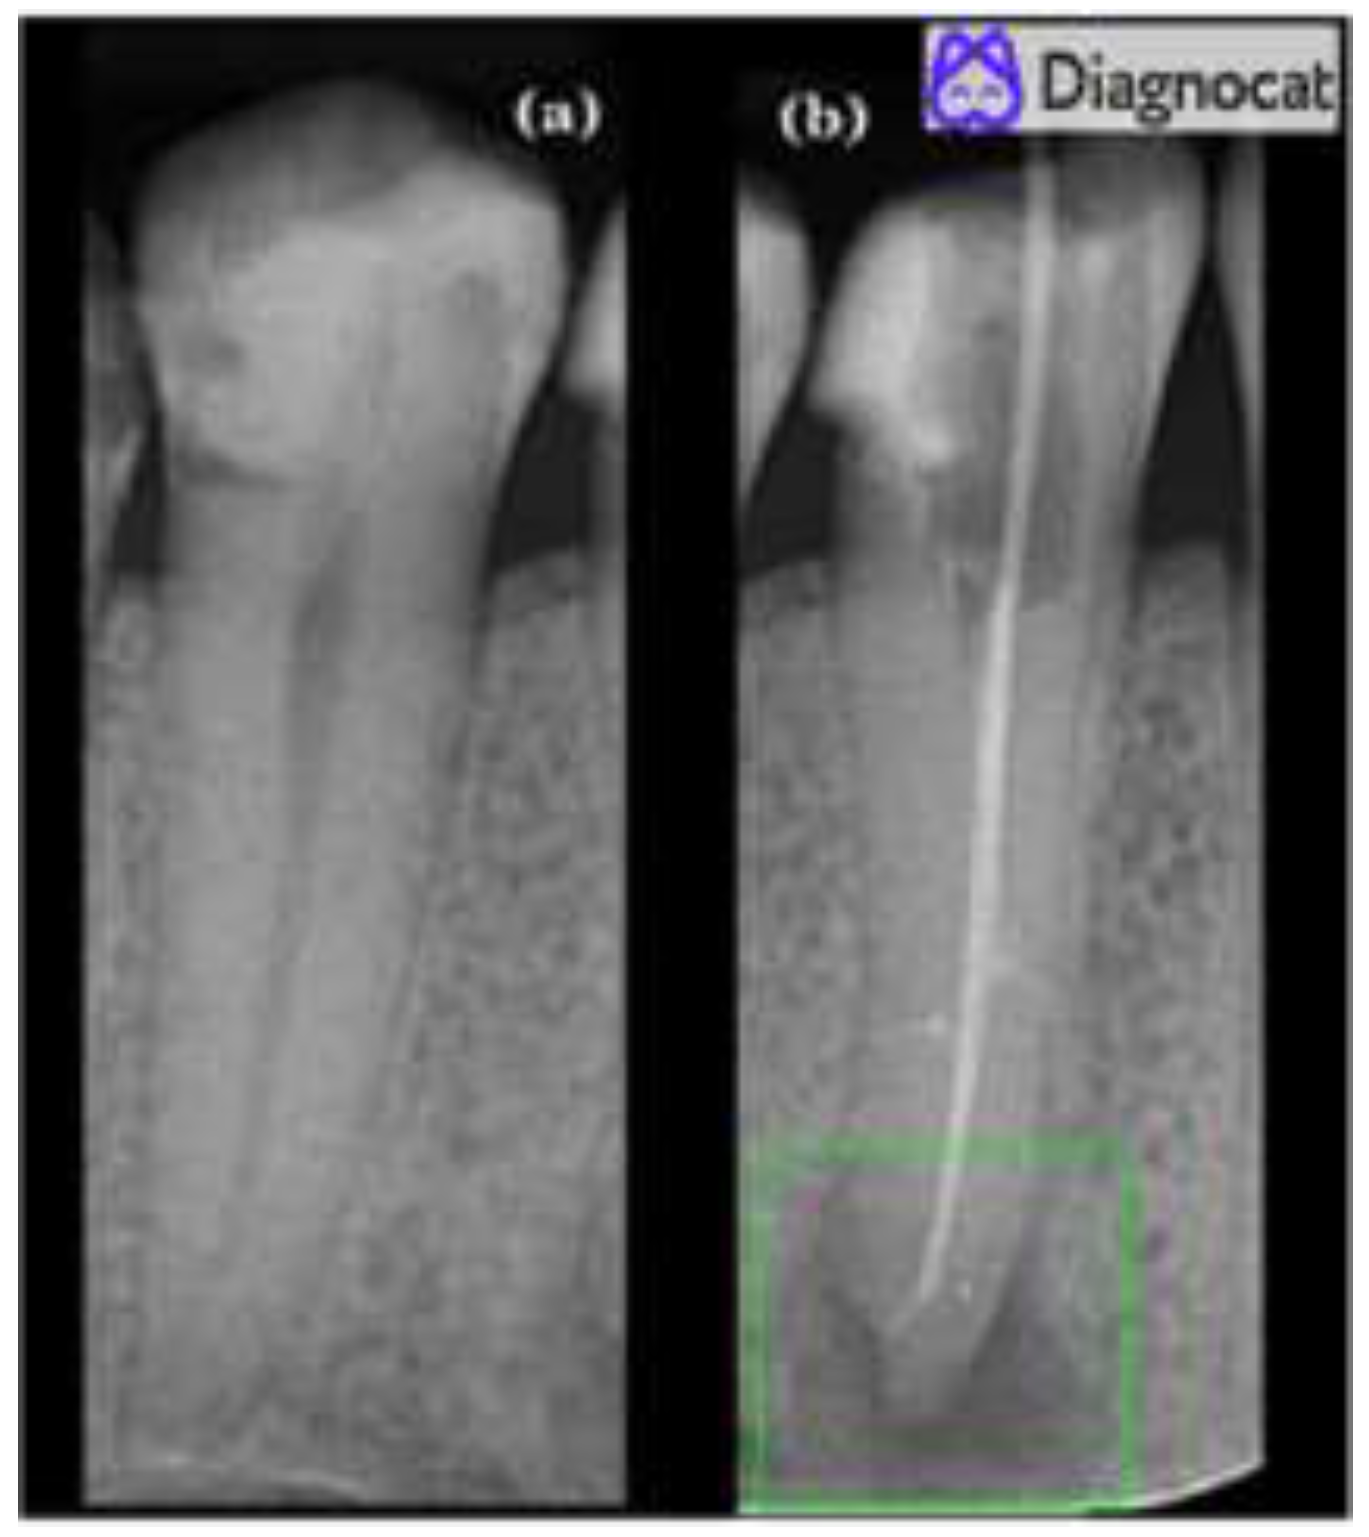

- Twelve true positives (TP) (teeth with apical periodontitis, unhealthy);

- One false positive (FP) (tooth with no signs of apical periodontitis was classified as unhealthy, over-diagnosed by the tool);

- Forty-six true negatives (TN) (healthy teeth, no signs of any apical periodontitis);

- One false negative (FN) (misdiagnosed by the tool; a tooth with apical periodontitis was classified as a healthy tooth).